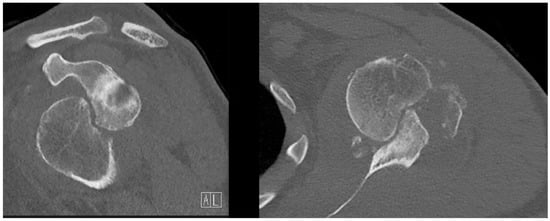

A radiographic assessment revealed an anterior dislocation in the glenohumeral joint, with a concomitant fracture of the greater tuberosity and a Hill-Sachs deformity as shown in Figure 1. The CT scan revealed a bony Bankart lesion of the anterior glenoid rim, and characterized the Hill-Sachs deformity to be large and off-track as shown in Figure 2. Due to the prolonged engagement with the glenoid rim during the 6 weeks that the head was dislocated, a substantial defect was mulled out. A graphic representation of this injury is presented in Figure 3. The patient was scheduled for surgery to be performed in the oncoming days.

Figure 2. Preoperative CT scan. Transversal (right) and coronal (left) frames of the affected shoulder showing the large Hill-Sachs deformity. On the coronal image, the Bankart lesion on the anterior glenoid rim is clearly visible.